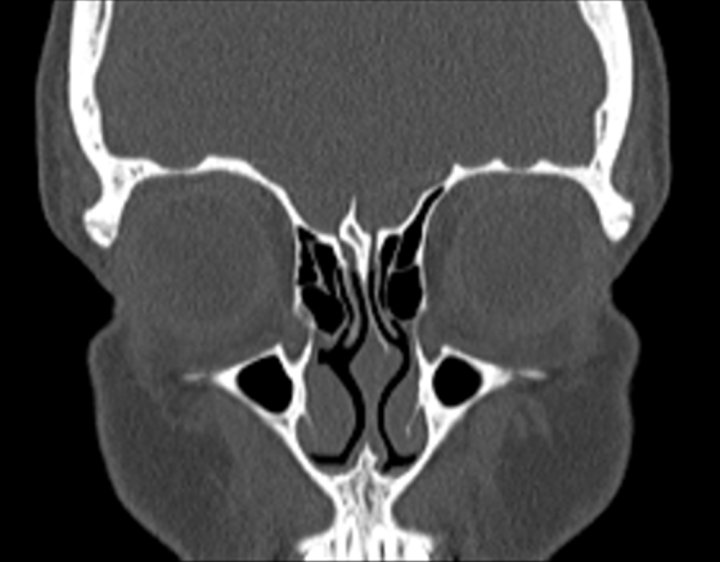

Click any image for labels.